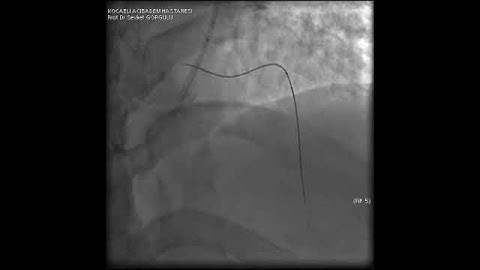

Microcatheter Tip Fracture During LAD CTO PCI: A Complication Video 3